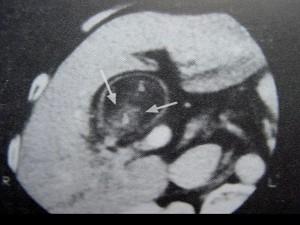

问题 男,55岁,上腹部隐痛一月余,CT检查如图,最可能的诊断是 ( )

选项 A、胆囊息肉 B、胆囊转移瘤 C、胆囊癌(腔内型) D、胆囊腺肌增生症 E、胆囊结石

答案 C